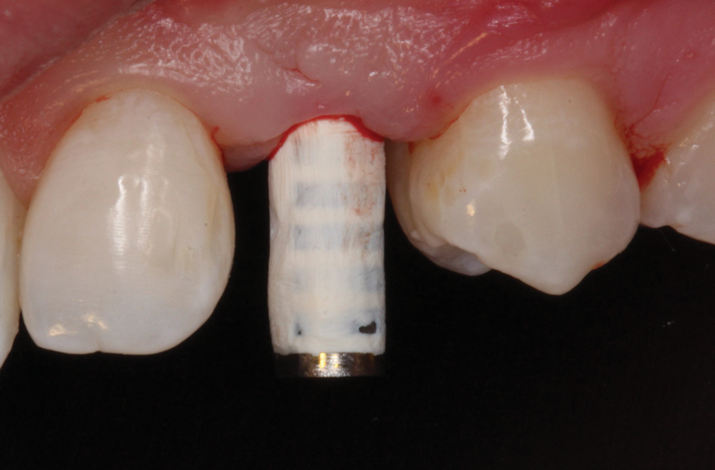

(38.) The opaqued titanium provisional abutment was gently tightened onto the implant.

Figure 38